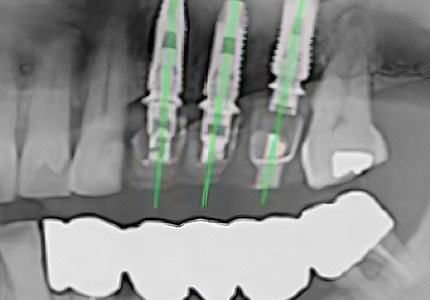

Guide-Assisted Surgery

The custom surgical guide is seated intraorally prior to surgery, enabling systematic placement at the planned position with minimal margin of error.

Natural implant placement at the simulation-planned position, with a prosthesis that feels just like your own natural tooth.

Surgery is performed through a small access opening just large enough for implant placement — without gingival incision — offering the advantage of minimal pain and faster recovery.